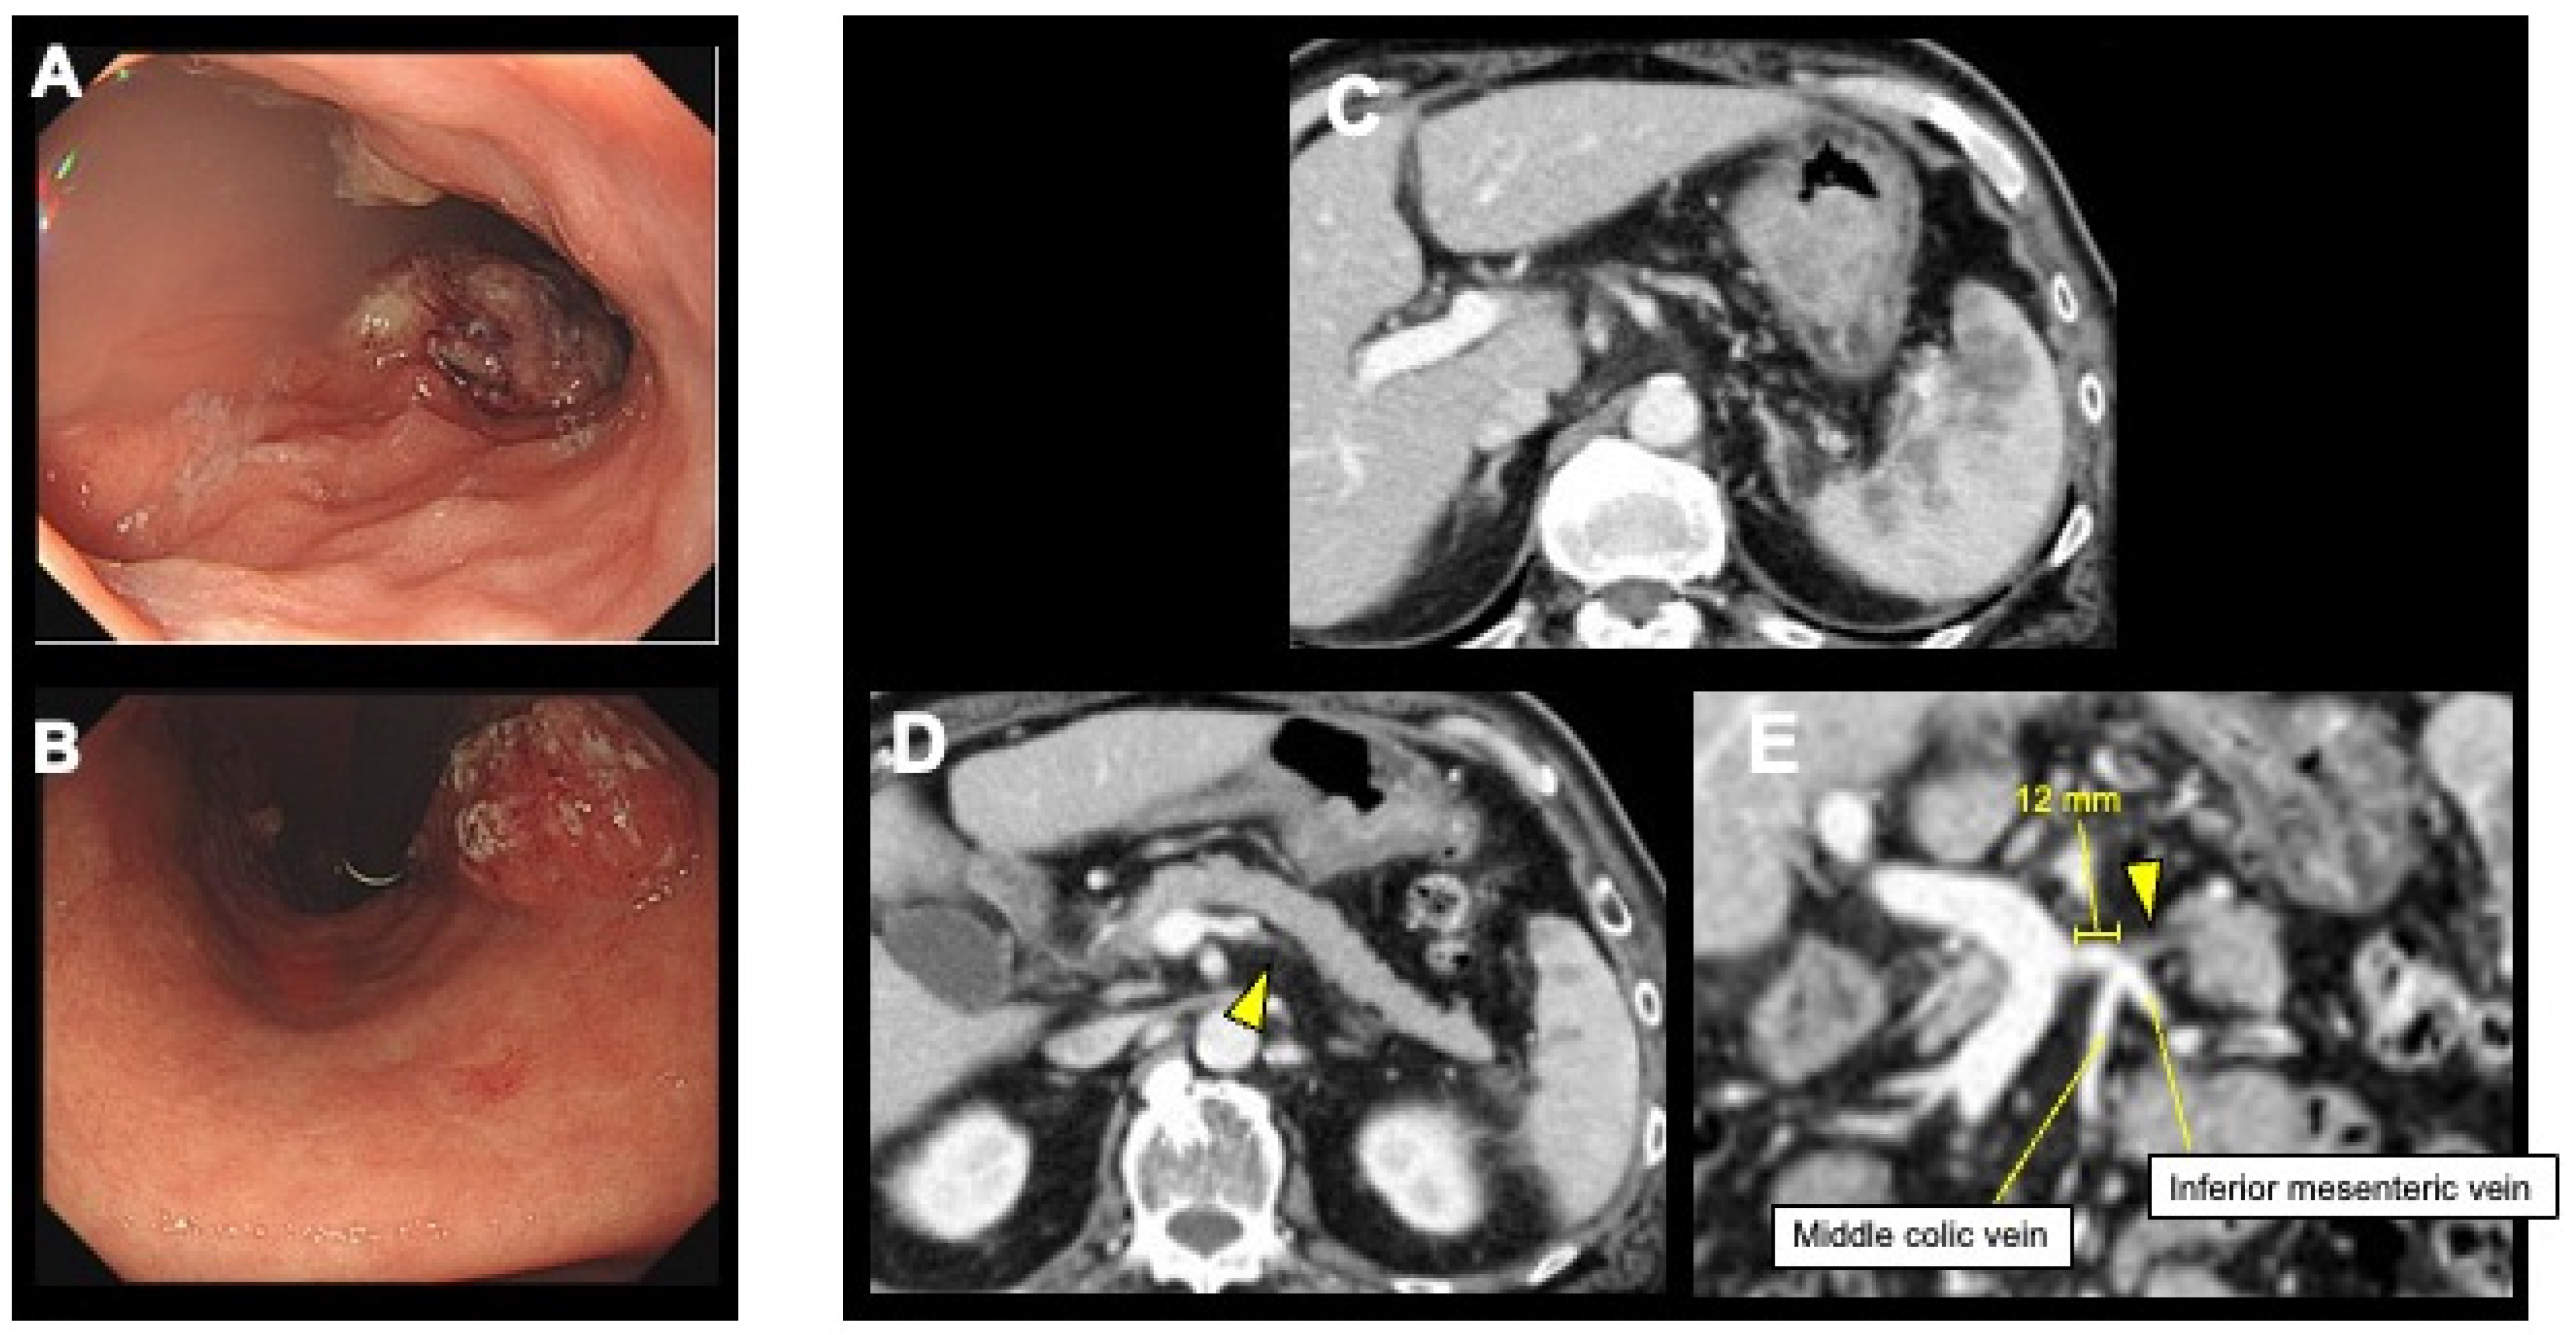

2. Case Presentation